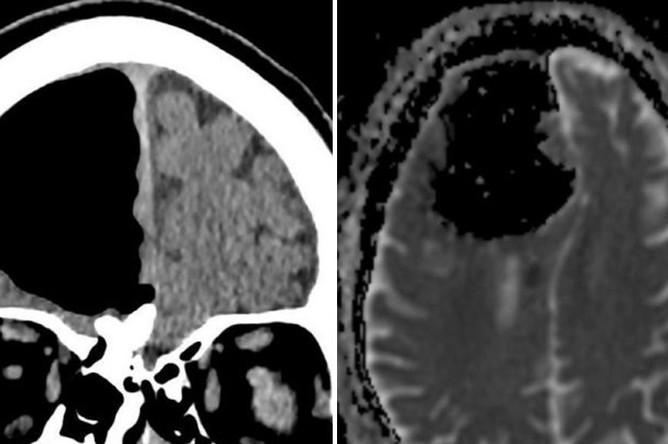

В миллиметре от смерти: ребенок выжил с шурупом в мозге

Нейрохирурги в США извлекли из черепа ребенка 15-сантиметровый шуруп